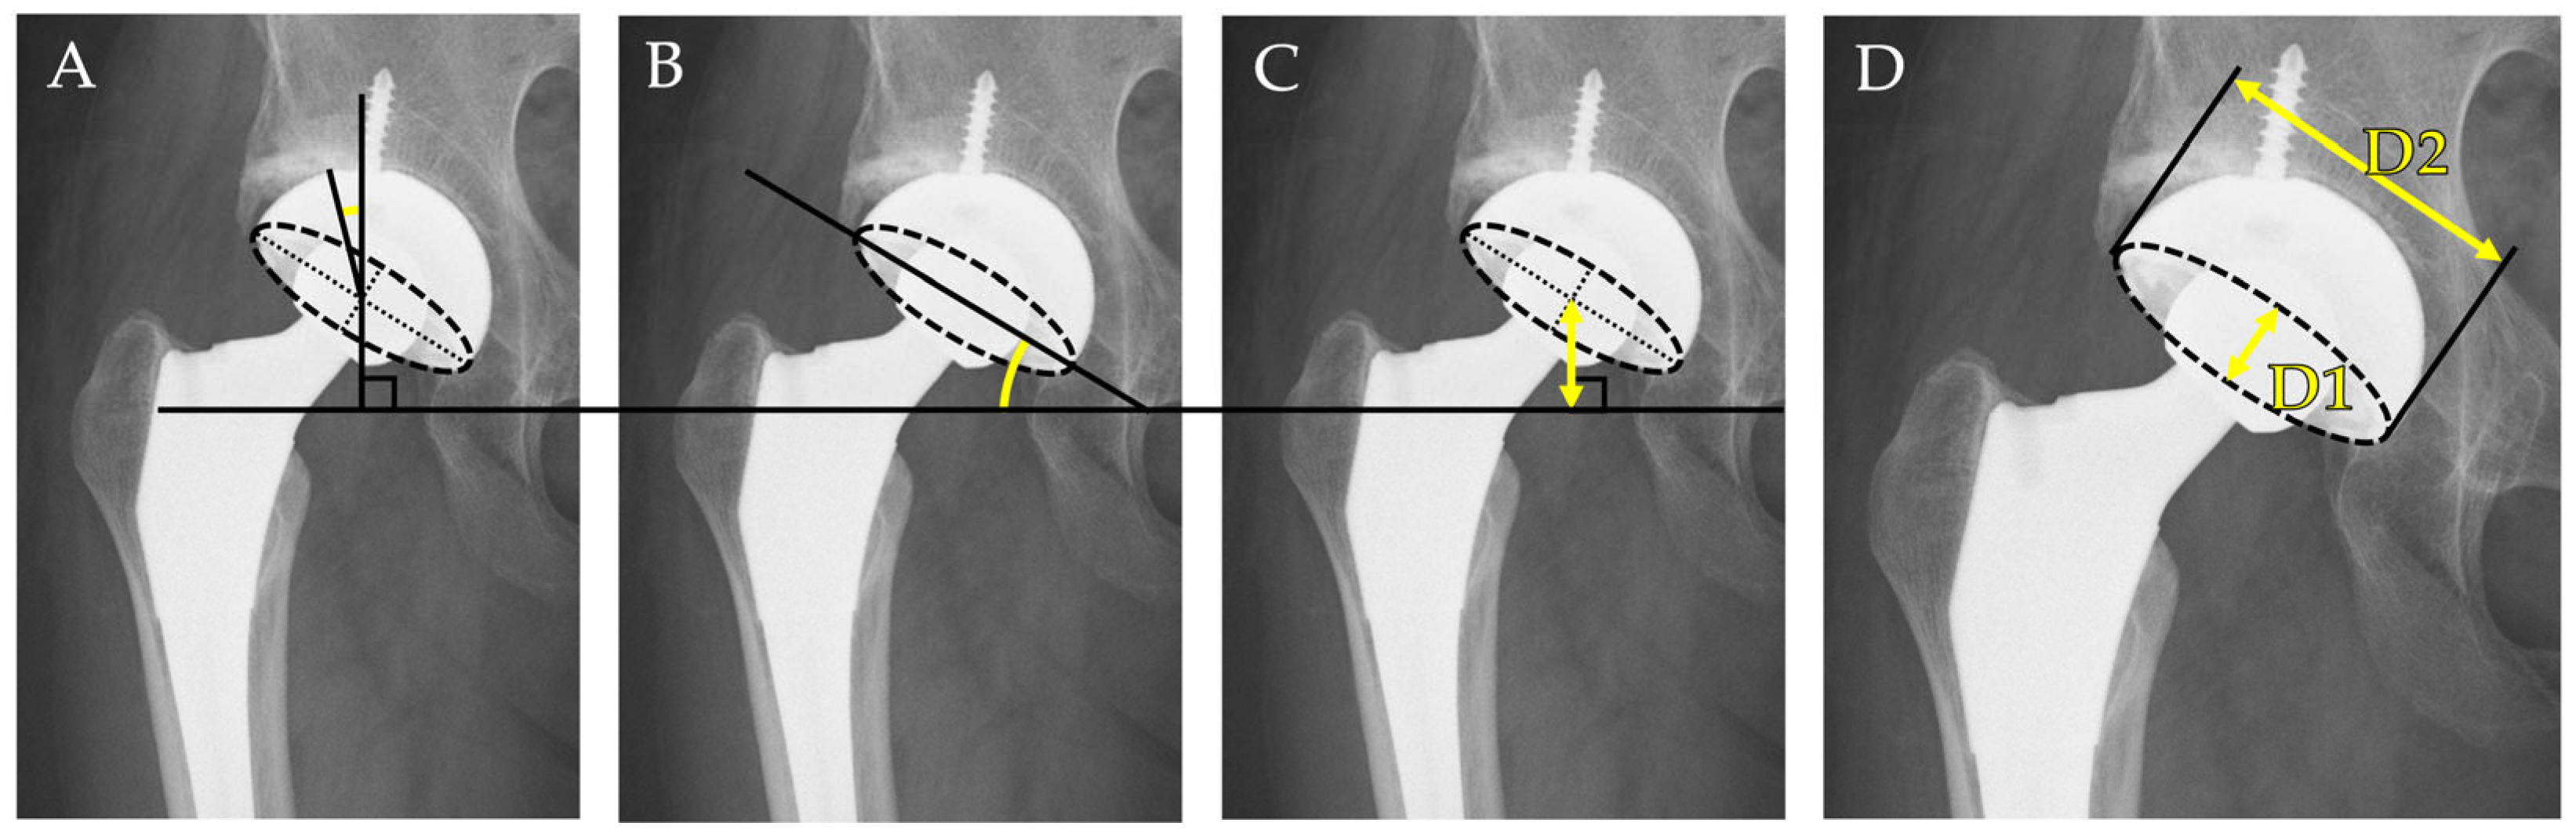

- Cup inclination angle: Defined as the angle between the inter-teardrop line and the opening face of the acetabular component. This reflects the abduction angle of the cup and was measured directly on the AP radiograph.

- Center-edge (CE) angle: Measured between a vertical line drawn from the center of the femoral head and a line connecting the femoral head center to the lateral edge of the acetabular cup. This parameter was used to evaluate the degree of lateral coverage of the implant.

- Cup height: Defined as the vertical distance between the center of the femoral head (or the prosthetic head) and the inter-teardrop line. In all cases, the inter-teardrop line was identifiable on standardized supine AP pelvic radiographs. In cases with mild distortion, contralateral bony landmarks and pelvic symmetry were used to confirm the accuracy of reference points.

- Radiographic anteversion: Estimated using Lewinnek’s method [25], calculated as the inverse sine of the ratio of the short axis (D1) to the long axis (D2) of the elliptical projection of the cup on the AP radiograph: